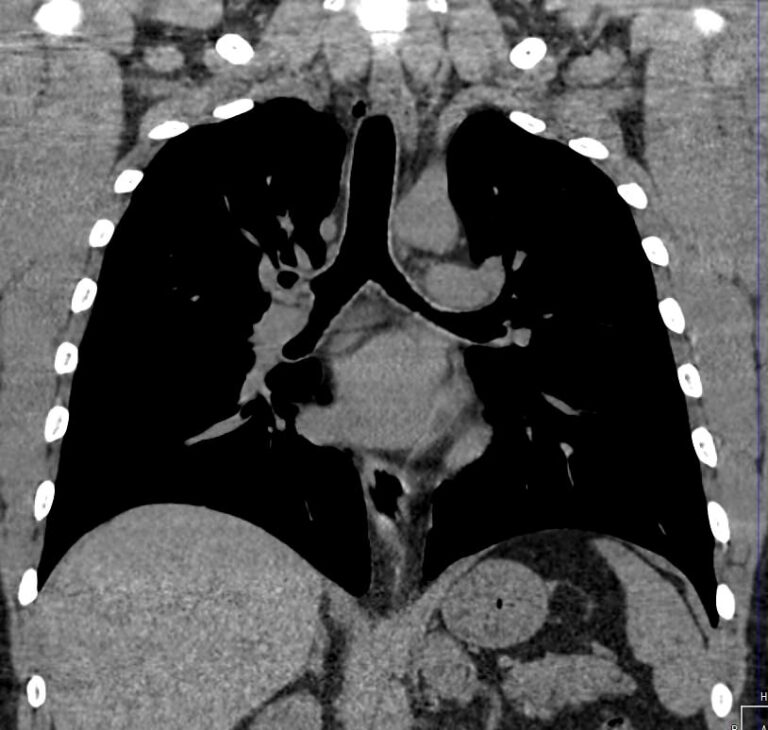

Средостение – анатомическое пространство в середине грудной клетки, которое с боков ограничено легкими, спереди грудиной, сзади позвоночником. В средостении располагаются органы, окруженные жировой клетчаткой, крупные кровеносные сосуды и нервы. К органам средостения относятся: пищевод, трахея, главные бронхи, вилочковая железа (тимус), сердце, аорта, верхняя и нижняя полые вены, нервы, лимфатические узлы.

Одним из наиболее информативных методов исследования органов средостения является компьютерная томография. В основе метода лежит использование проникающего действия ионизирующего излучения для получения подробных снимков строения внутренних органов.

Инновационные технологии, которыми оснащены компьютерные томографы, послойно сканируют анатомическую область с шагом от 0,5 мм. В результате получаются снимки тонких срезов исследуемой зоны в мельчайших подробностях. С помощью цифровых приложений на основании полученных данных можно реконструировать трехмерные модели внутренних органов, что позволяет оценить структуру зоны исследования и близлежащих тканей.

- подозрение на аневризму (расширение) аорты, для выявления патологии крупных сосудов средостения (верхней и нижней полых вен, легочных вен и артерий).

- аневризмы аорты и ее плечеголовных ветвей;

- аневризму аорты